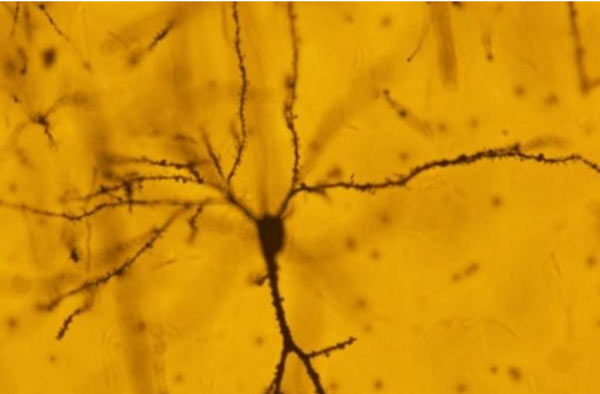

যে স্নায়ুকোষে জমা হয় স্মৃতি। অণুবীক্ষণের নীচে।

মস্তিষ্কের পিরামিডাল নিউরন